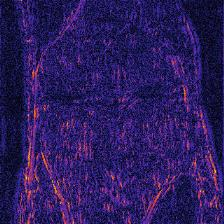

Recently, deep neural networks have greatly advanced undersampled Magnetic Resonance Image (MRI) reconstruction, wherein most studies follow the one-anatomy-one-network fashion, i.e., each expert network is trained and evaluated for a specific anatomy. Apart from inefficiency in training multiple independent models, such convention ignores the shared de-aliasing knowledge across various anatomies which can benefit each other. To explore the shared knowledge, one naive way is to combine all the data from various anatomies to train an all-round network. Unfortunately, despite the existence of the shared de-aliasing knowledge, we reveal that the exclusive knowledge across different anatomies can deteriorate specific reconstruction targets, yielding overall performance degradation. Observing this, in this study, we present a novel deep MRI reconstruction framework with both anatomy-shared and anatomy-specific parameterized learners, aiming to "seek common ground while reserving differences" across different anatomies.Particularly, the primary anatomy-shared learners are exposed to different anatomies to model flourishing shared knowledge, while the efficient anatomy-specific learners are trained with their target anatomy for exclusive knowledge. Four different implementations of anatomy-specific learners are presented and explored on the top of our framework in two MRI reconstruction networks. Comprehensive experiments on brain, knee and cardiac MRI datasets demonstrate that three of these learners are able to enhance reconstruction performance via multiple anatomy collaborative learning.

翻译:最近,深心神经网络大大推进了未经充分取样的磁共振成像(MRI)重建,其中大多数研究都遵循单一解剖一个网络的方式,即每个专家网络都经过特定解剖学的培训和评价。除了在培训多种独立模型方面效率低下之外,这种公约忽视了不同解剖学中共享的、可相互受益的解析知识。为了探索共享知识,一种天真的方法是将各解剖学家的所有数据结合起来,以训练一个全方位网络。不幸的是,尽管存在共享的解析知识,但我们发现,不同解剖学的独家知识可以恶化具体的重建目标,导致总体性能退化。在这项研究中,我们提出了一个新型的深度解剖重建框架,既有解剖学共享知识,又具有具体的解剖学参数,目的是“寻找共同的土壤,同时保留不同解剖学家之间的差异。此外,主要的解剖学学习者将接触不同的解剖学数据,通过多种解剖学重建的模型,并用不同的解剖学研究者将数据展示出一个全方位基础。